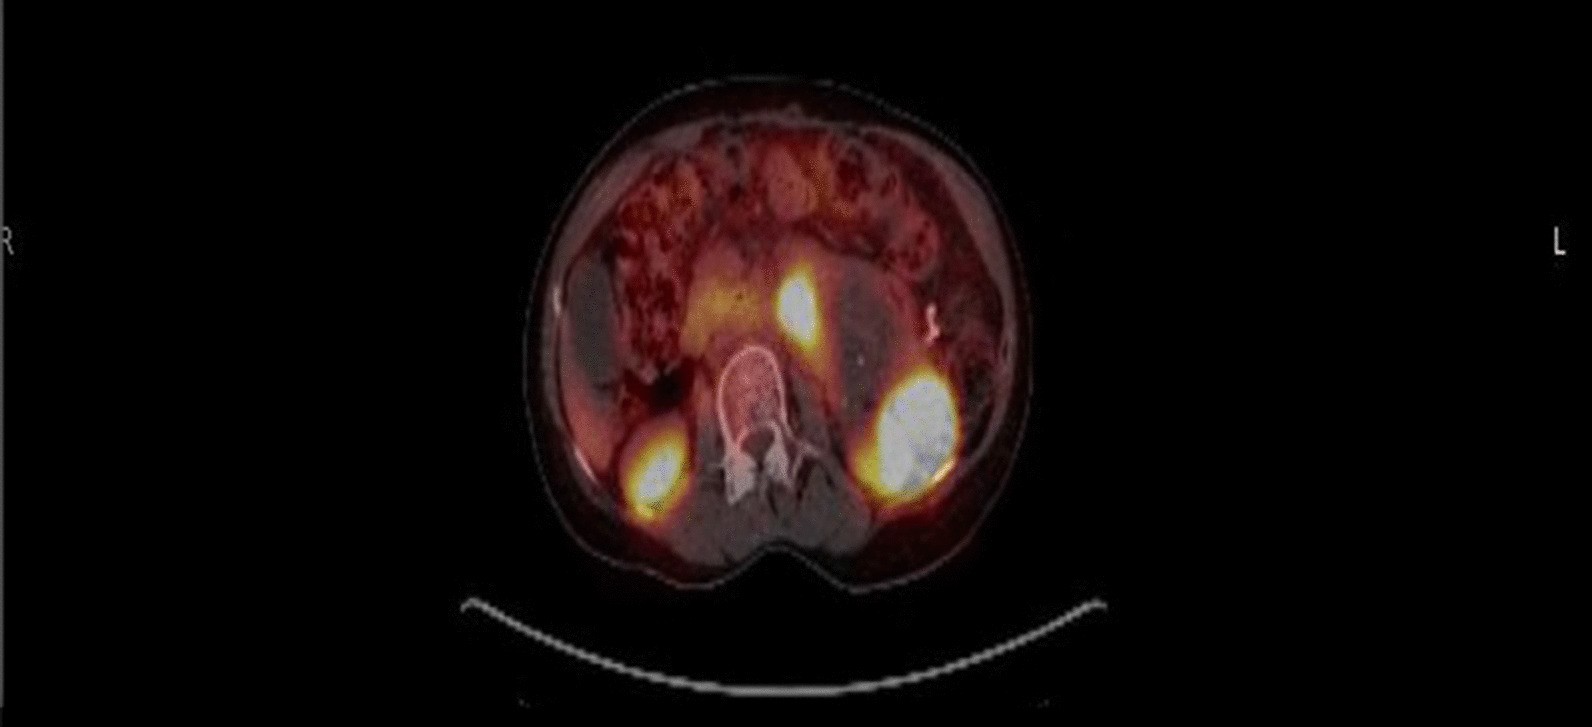

PET restaging scan demonstrating SSR positivity